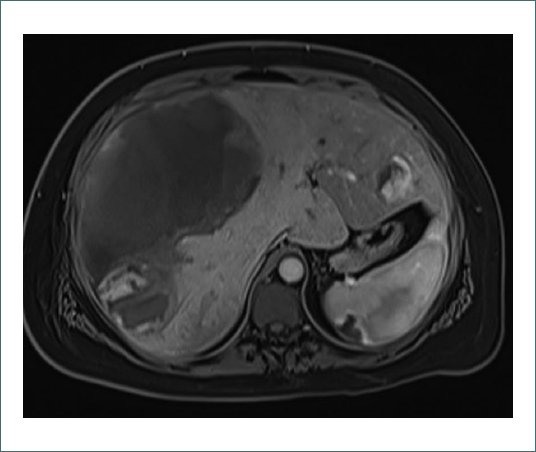

Después del procedimiento, persiste dolor de difícil control que requiere escalada analgésica siguiendo el protocolo hospitalario desde paracetamol 1g/8h + metamizol 1g/8h alternados + ibuprofeno 400mg/8h hasta PCA endovenosa (Analgesia Controlada por el Paciente) de morfina a dosis reducida (5 mg cada 10 minutos). A pesar de la optimización analgésica, la paciente sigue presentando un EVA 8 y se solicita valoración por Unidad del Dolor para un abordaje multidisciplinar. Se ajusta pauta analgésica con gabapentina en pauta ascendente hasta 600 mg/8h + duloxetina 30 mg/24 h + clonazepam 0,5 mg/24 h. Se aumenta PCA a pauta estándar (10 mg cada 10 minutos). A pesar de los ajustes previos, la paciente continúa con dolor intenso y la exploración no reporta cambios. Analíticamente la paciente presenta una buena evolución, sin signos de anemización ni elevación de parámetros inflamatorios. El perfil de transaminasas sigue una curva descendente. Se completa estudio de imagen con resonancia magnética nuclear (RMN) (Figs. 1 y 2).

Figura 1. Corte axial de RMN hepática en secuencia T1 con saturación grasa y tras la administración de contraste, en fase arterial-precoz. Se evidencia hematoma de aproximadamente 15x12x19 cm (APxLxCC), con márgenes irregulares de predominio en segmentos anteriores del lóbulo hepático derecho y que se extienden hacia segmentos posteriores, así como segmento 4. En lóbulo hepático izquierdo se observa otro adenoma con captación típica en fases arteriales precoces.